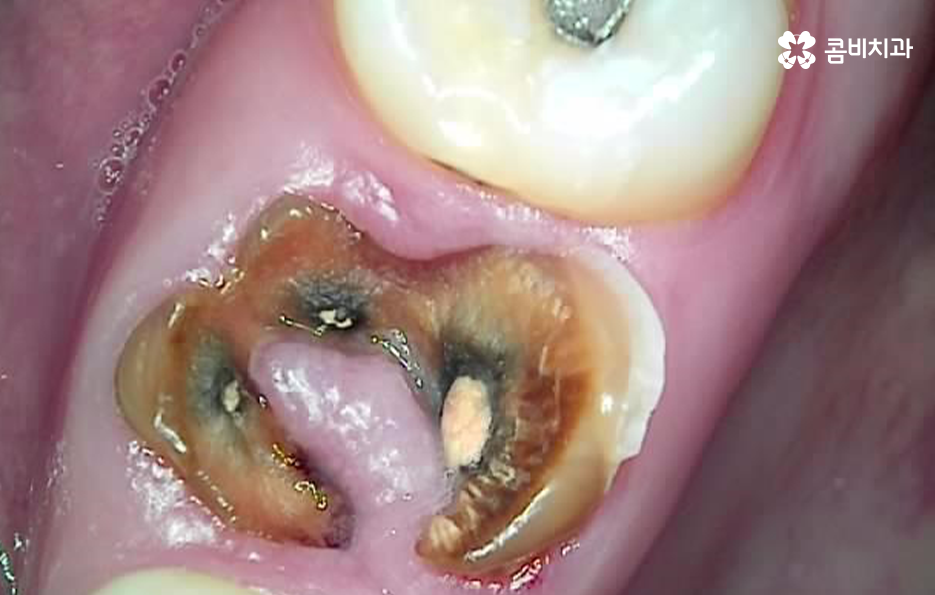

우선 충치가 신경조직까지 진행된 경우를 먼저 살펴보면 신경에 도달한 충치는 보통 극심한 시림과 통증을 느끼게 할 거예요. 충치의 단계로 비교하자면 법랑질에 발생한 충치의 경우 별다른 증상을 못 느끼는 경우가 대부분인 반면에 신경에 충치가 도달하면 시림이나 통증이 매우 크다고 느낄 정도이며 심한 경우 일상생활이 어렵고 잠을 자기 어려울 정도로 불편함도 느낄 거예요. 그리고 간혹 선천적으로 신경이 뾰족한 경우가 있는데, 이 경우 신경이 노출되지 않아도 차가운 물을 먹을 때 시리거나 저작 시 통증이 발생할 수 있는데, 이 경우에도 신경치료 필요하고, 방치할 경우 신경이 변형되거나 죽으면서 뿌리 쪽에 염증이 생기는 경우가 있어요.

이처럼 충치로 인해 신경치료가 필요한 경우에는 참지 마시고 치료를 빠르게 받는 것이 일상생활과 건강을 위해서도 필요하며 자연치아의 보존에 있어서도 권장하고 있어요

두 번째 경우로는 뿌리 끝에 염증이나 고름이 발생한 경우에 진행하는 신경치료의 케이스인데 이러한 경우에는 충치가 신경에 도달하여 느끼는 통증과는 달리 통증을 크게 못 느끼는 경우도 있는데요.

보통 뿌리 끝에 발생한 염증이나 고름의 경우 엑스레이 등의 검사를 통해 발견된 문제로 신경치료가 필요한 케이스인데 환자분의 입장에서는 당장 불편함을 크게 못 느끼고 신경치료를 하려면 치과에 여러 번 방문해야 하기 때문에 치료를 미루는 경우도 많이 있어요.

뿌리 끝에 발생한 염증의 경우 불편함을 못느끼더라도 빨리 치료하는 것이 좋은 이유는 시간이 지날수록 작았던 염증은 점점 커지게 되고 잇몸 뼈를 녹게 만들어 치아가 결국 흔들리게 될 수 있고, 당장 통증이 없더라도 치료 시기를 놓쳐, 일정 수준 이상으로 진행이 된 경우 급성치수염 증상으로 진통제를 먹어도 통증이 잡히지 않을 정도로 극심한 통증이 동반될 수 있습니다.

잇몸 뼈에 문제가 생겨 치아가 흔들리게 되면 보통 치료의 골든타임을 놓치게 되기 때문에 이때는 신경치료를 시도할 수도 없고, 치근단절제술이나 치아재식술을 시도해 볼 수 있지만, 성공 확률이 높지 않기 때문에 치아를 발치해야 하는 경우가 대부분이라고 할 수 있어요